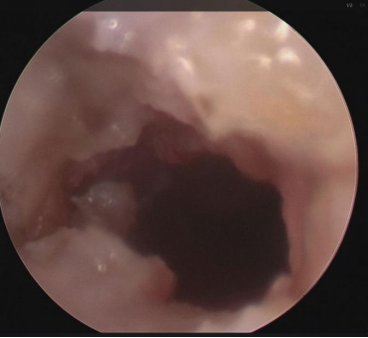

▲ 闭锁的声门下气管被打开

那么,怎么保证这好不容易打通的声门不再闭锁呢?

按术前讨论,并和病人家属充分沟通后的决定,团队的医生们在闭锁打通的部位放了一个药物支架,在这之前,世界上还没有医生用这种方法去治疗这种疾病。

这个支架有弹力,属于生物可降解材料,它释放出来的药物能防止伤口发炎、粘连。

▲ 植入的药物支架

术后当天,丁丁哭笑都有声音了,尽管言语还需要逐步提高,但这个声音对家长来说,是天籁之音没错了。

自此,丁丁有两条「气道」,除了原先的「吊坠」,他也能像正常人一样通过鼻子和嘴巴去呼吸了。

更重要的是,他可以学说话了。

▲ 植入药物支架后的声门下